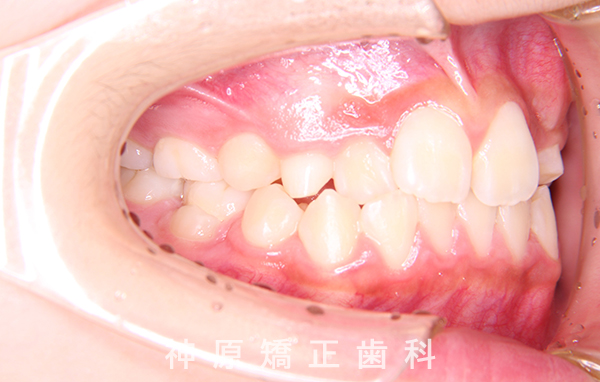

初診時

上のあご(上顎)の右側の犬歯について、歯の生えてくる方向に異常が見られました。そのため、歯ぐきを一部開いて、犬歯を正しい位置に引っ張り出す「開窓牽引」という処置を行いました。

その後、マルチブラケット装置を使い、歯を抜かずにきれいに並べる矯正治療を行いました。